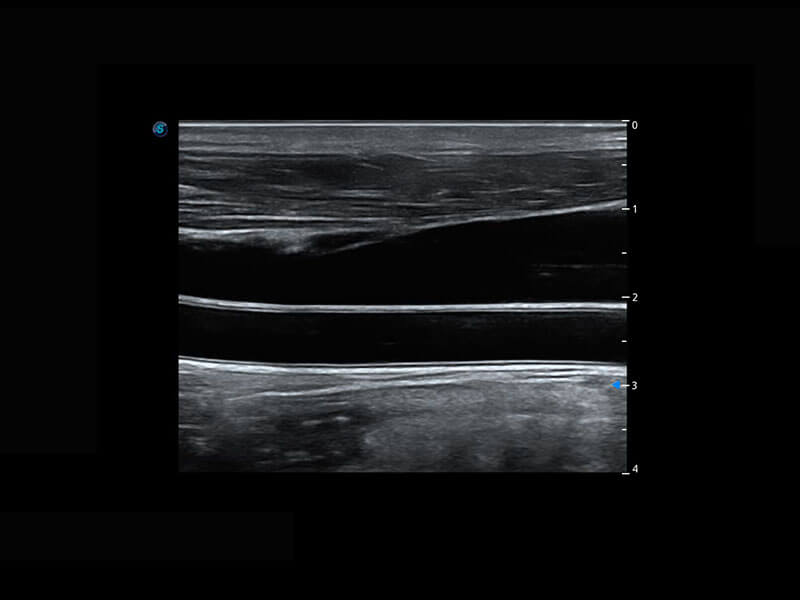

新生儿脊髓圆锥